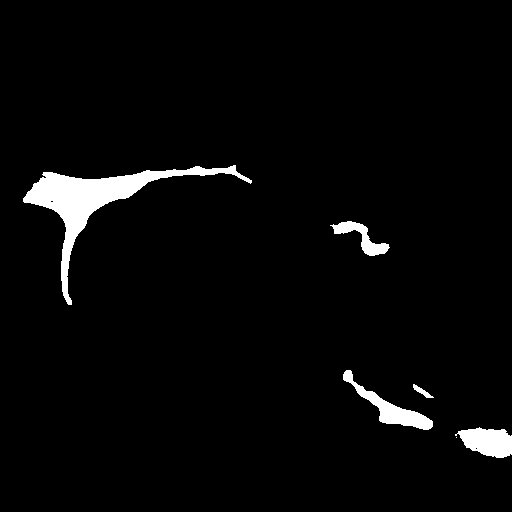

3.5 Failure Cases

In Figure 3, we illustrate failure cases in dataset . In the first example, AURA-net fails to correctly segment the bottom part of the object. This outcome is unsurprising considering that the raw image exhibits a lower SNR than any of the training data. In the second example, the segmentation mask predicted by AURA-net contains several objects, yielding a poor overlap with the ground truth annotation featuring a single cell. However, the original image reveals the presence of a second, partially cropped non-annotated cell. In this case, part of AURA-net’s “false” detection are actually correct predictions that have been omitted in ground truth annotations.